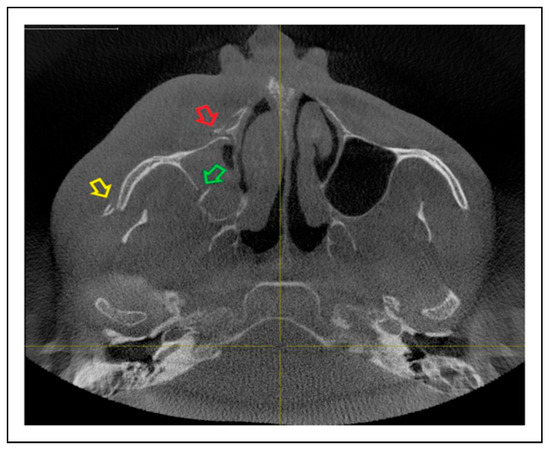

Patterns of ZMO Fractures Regarding the Anatomic Sutures of the Zygoma

- Unisutural fracture (isolated fracture of a single anatomic suture of the zygoma):

- Zygomaticomaxillary suture (ZM)

- Infraorbital rim (IOR)

- Zygomaticofrontal suture (ZF)

- Zygomaticosphenoidal suture (ZS)—the anterolateral orbital floor

- Zygomaticotemporal suture (ZT)

- Bisutural fracture with the following fracture line combinations:

- Trisutural fracture with the following fracture line combinations: